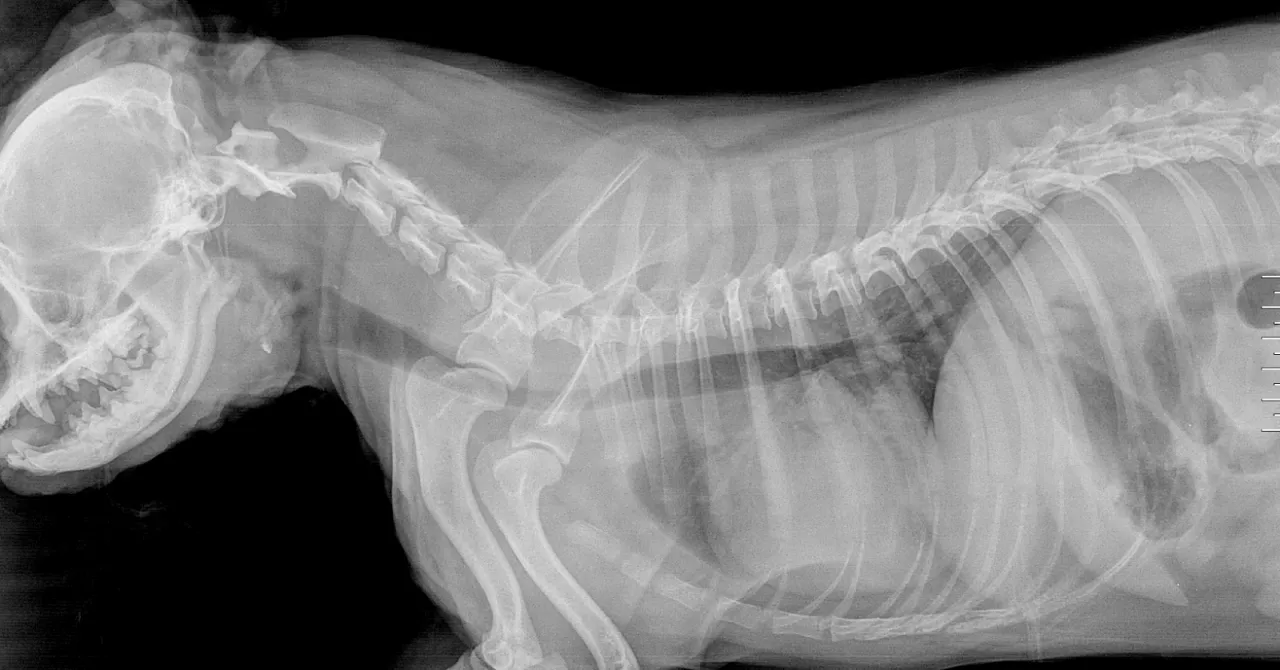

RTG klatki piersiowej: Co można zobaczyć na prześwietleniu?

Zdjęcie rentgenowskie (RTG) klatki piersiowej to często pierwsze badanie obrazowe, które wykonujemy. Może ono uwidocznić zwężenie tchawicy, jednak jego czułość nie jest stuprocentowa wynosi około 60%. Oznacza to, że prawidłowy wynik RTG nie wyklucza całkowicie zapadającej się tchawicy. Aby uzyskać jak najwięcej informacji, wykonuje się zdjęcia w różnych fazach oddechu: zdjęcie odcinka szyjnego tchawicy na wdechu, a piersiowego na wydechu. Pozwala to ocenić dynamikę zmian i stopień zapadania się w zależności od fazy oddechowej.